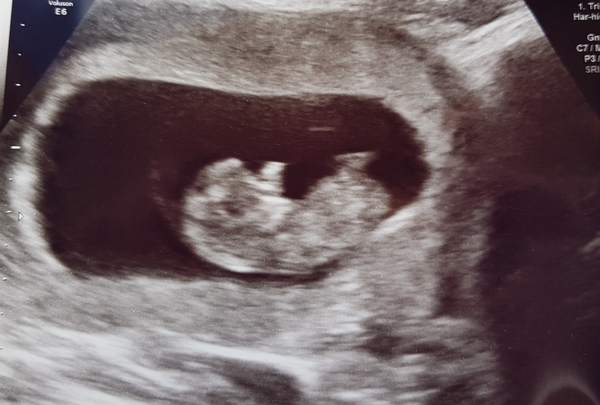

MrsTeaPlease · 21/05/2018 19:55

All went well at my scan on Saturday. Was measuring 10+4 So 10+6 today. Baby even had hiccups during the scan! Thought I would post it incase anyone is interested and a similar gestation as I know I was interested to see others.

@MrsTeaPlease I'm 10+6 today too! Hello bump buddy 🤰👍🏻

Gorgeous scan @mrsteaplease